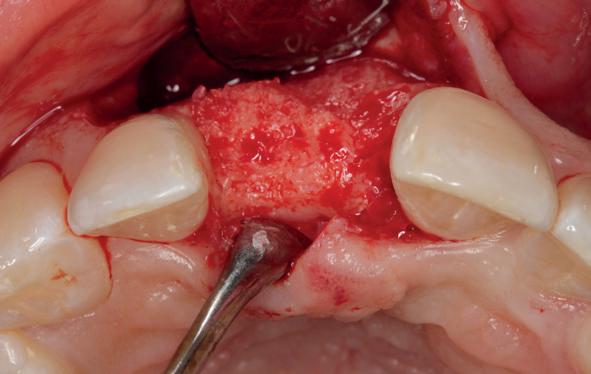

Implantologische behandelingen in het esthetische front vragen meer dan technische vaardigheid alleen. Ze vragen om overzicht, timing, vertrouwen en een team dat als vanzelf samenwerkt onder druk. Juist bij complexe casussen, waarin angst, infectie en hoge esthetische verwachtingen samenkomen, wordt zichtbaar hoe bepalend de rol van de tandartsassistent is.

Deze casus beschrijft een uitgebreide immediate implantaatbehandeling bij een patiënt die door meerdere collega’s werd geweigerd. Niet omdat de mogelijkheden ontbraken, maar omdat de complexiteit vroeg om een perfect afgestemde samenwerking. Het verhaal laat zien hoe de assistent in zo’n traject veel meer is dan een uitvoerende kracht of “mal”, maar een dynamische surgical guide die het proces mede stuurt, bewaakt en mogelijk maakt.De patiënt: wanneer alles samenkomt

Na het klinische onderzoek volgde het röntgenologisch traject. De CBCT liet precies zien wat we al vreesden: een front waarin het bot onregelmatig was, duidelijke radiolucenties rond de pijlers en een infectiegebied dat zich onder vrijwel de gehele brug had verspreid. Tegelijkertijd was er ook potentie. Net voldoende botstructuur om immediate implantaatplaatsing te overwegen, mits alles perfect gepland zou worden.